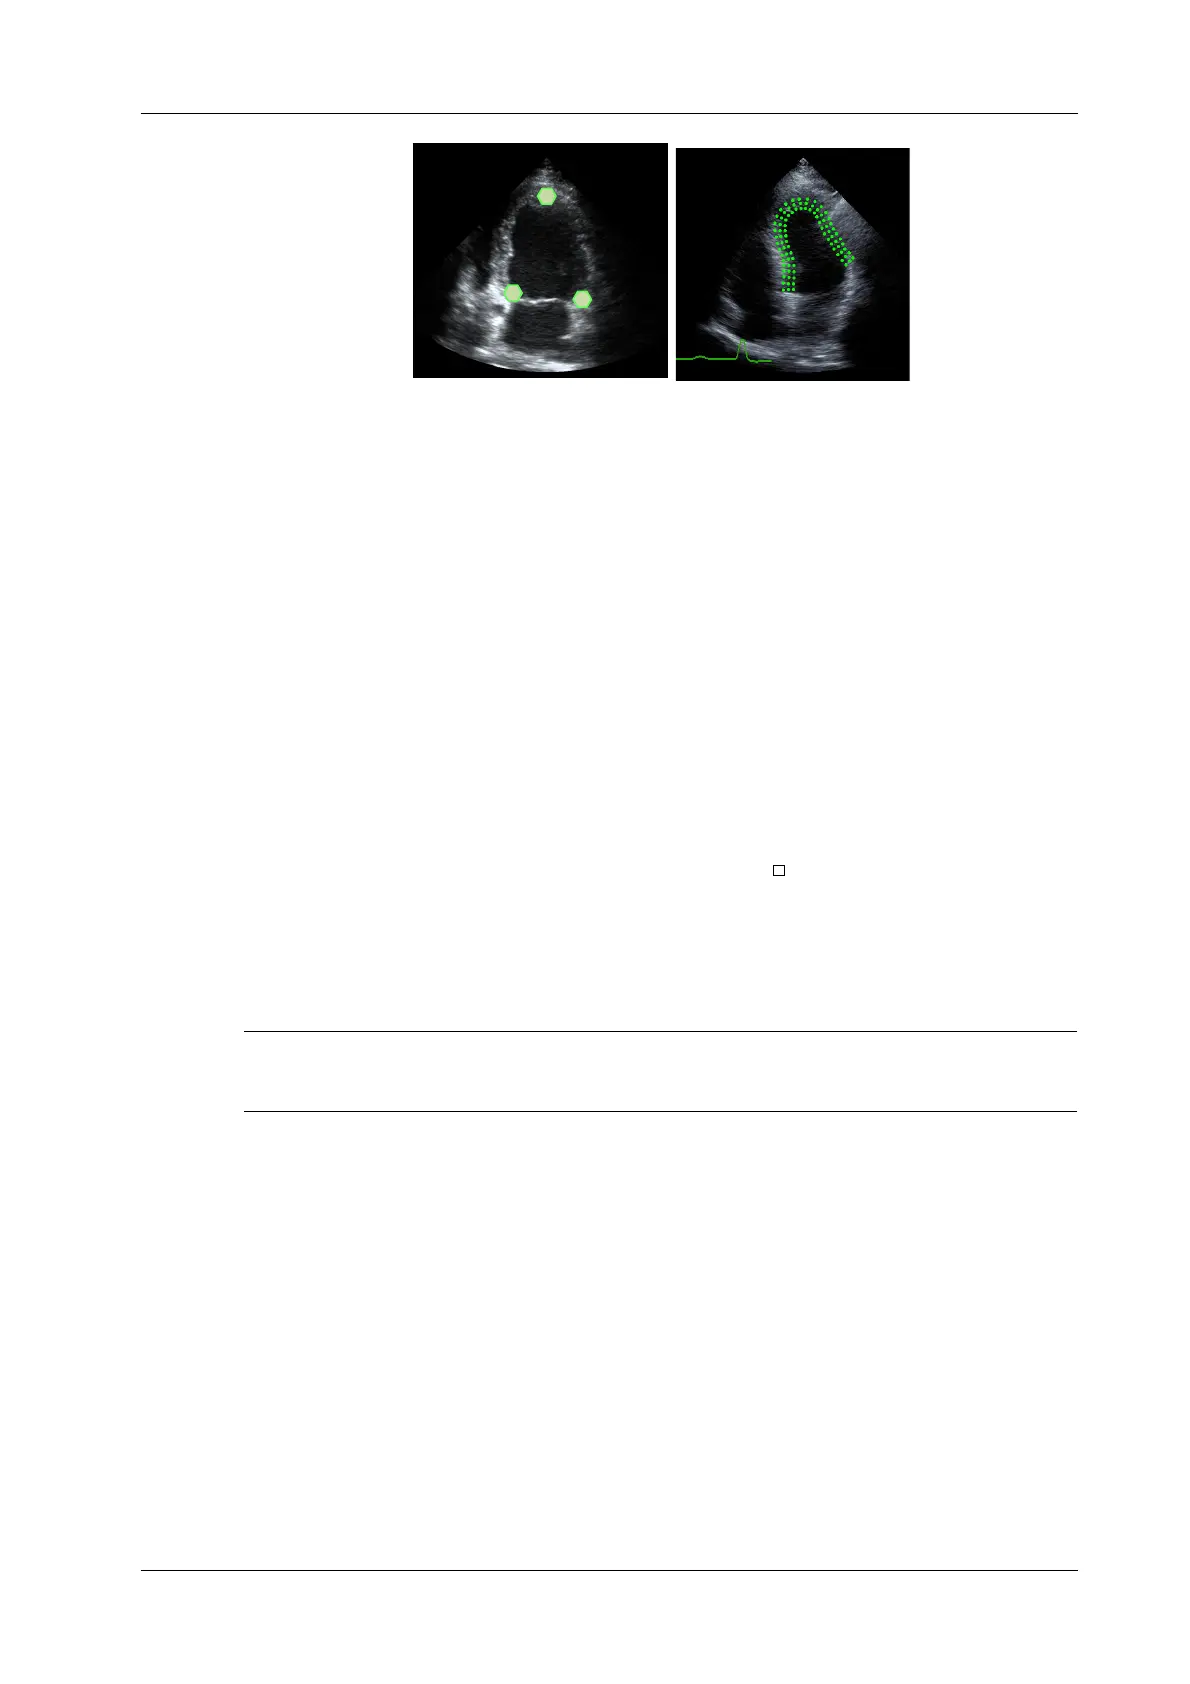

Manual trace method

Press <Set> and move the cursor by using the trackball/trackpad along the boundary to add the

trace points gradually, after trace is finished, press <Set> twice to finish tracing.

At least 6 points should be determined by you before the system generates automated trace.

Press <Set> to make the traces on the image clockwise or anticlockwise.